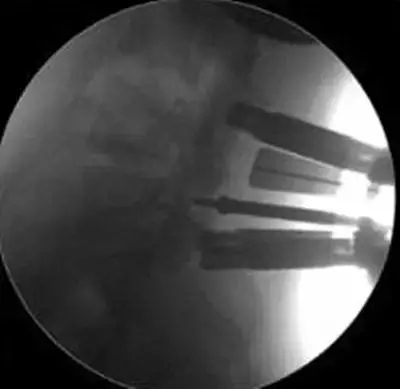

劉志安副院長(zhǎng)所說(shuō)的“微創(chuàng)小切口”就是通道下髓核摘除植骨融合經(jīng)皮內(nèi)固定術(shù)。其原理就是利用MIS-TLIF技術(shù)微創(chuàng)治療腰椎疾病,不但能達(dá)到開(kāi)放手術(shù)的效果,且切口及創(chuàng)傷為開(kāi)放切口的1/3,術(shù)中出血量少,患者術(shù)后可以恢復(fù)更快。

據(jù)劉院長(zhǎng)介紹,MIS-TLIF技術(shù)是經(jīng)椎旁肌間隙入路運(yùn)用脊柱內(nèi)鏡或?qū)S猛ǖ佬醒甸g盤(pán)切除、椎管減壓、植骨內(nèi)固定術(shù),是一項(xiàng)應(yīng)用廣泛、技術(shù)成熟的脊柱微創(chuàng)手術(shù)方法。本技術(shù)可以完成與傳統(tǒng)手術(shù)完全相同的椎間盤(pán)切除、椎間植骨融合內(nèi)固定等操作。手術(shù)切口一般3-5厘米,本手術(shù)方式可有效避免傳統(tǒng)手術(shù)對(duì)腰背肌肉的損傷,患者術(shù)后腰背部疼痛輕、恢復(fù)快,手術(shù)效果優(yōu)于傳統(tǒng)手術(shù),治療后1-3天即可下床活動(dòng)。本技術(shù)適于大部分的腰椎間盤(pán)突出癥、腰椎管狹窄癥、腰椎滑脫癥等。